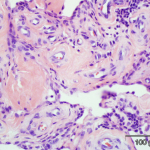

Histopathology

CBI offers histology and pathology, incuding immunohistochemistry, plastics, devices and histomorphometry in both a GLP and nonGLP environment for studies generated within CBI as well as from animals from field and academic studies. We welcome tissues from both companion animals and large farm or exotic animals.